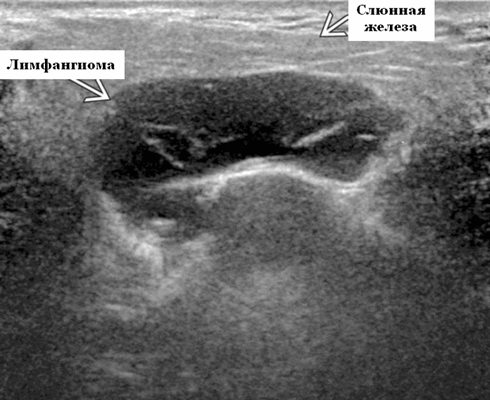

Околоушная лимфатическая мальформация

Синонимы. Пороки развития сосудов лимфатического типа. Спектр болезней. Венолимфатическая мальформация (ВЛМ): элементы венозной сосудистой мальформации (ВСМ) и ЛМ в одном и том же образовании. Лимфангиома и кистозная гигрома (старые термины)

Определение. Аномальное скопление расширенных лимфатических каналов, выстланных эндотелиальными клетками. Почти все они врожденные, возникшие в результате аномального развития лимфатической системы. Очень редко может быть вторичным по отношению к травме или операции.

- Расположение. 75% возникают в области головы и шеи (наиболее часто). На подъязычной области шеи ЛМ чаще всего встречаются в заднем треугольнике, тогда как жевательные и поднижнечелюстные пространства - самые частые места надподъязычной зоны шеи. Интрапаротидное расположение встречается нечасто, при этом поражение может быть транспространственным, затрагивая несколько смежных пространств. 20% поражают опухолей подмышечную впадину. Реже поражается средостение, пах и забрюшинное пространство.

- Размер. Переменный, на УЗИ может быть большим и обширным

- Морфология. Однокамерное или, чаще, многокамерное поражение. Может содержать округлые или вкрапленные кистозные пространства. Имеет тенденцию проникать между нормальными структурами без какого-либо масс эффекта

Результаты ультразвукового исследования. Серошкальное УЗИ. Более крупные околоушные лимфангиомы могут быть обнаружены при пренатальном УЗИ. Чаще мультилокулярный, чем монокулярный. Кистозные пространства могут быть округлыми или вкраплениями. Поверхностные поражения сжимаются ультразвуковым датчиком. Внешний вид зависит от того, было ли ранее кровотечение / инфекция. Негеморрагический / неинфицированный лимфаангимоы выглядят на УЗИ как однокамерные или многокамерные (чаще) анэхогенные сжимаемые кисты с тонкими стенками и промежуточными септами. Несмотря на большие размеры, существенного масс эффекта нет. Тонкие незаметные стенки с задним акустическим усилением. Цветной допплер: в области поражения нет кровеносных сосудов. Геморрагический / инфицированный тип лимфатической мальформации. Однокамерные или многокамерные гетерогенные кисты с неровными стенками, внутренним дебрисом. Несжимаемые датчиком и гипоэхогенные полости с толстыми стенками и перегородками. Уровни жидкости-жидкости из-за осаждения и разделения жидкостей предполагают предшествующее кровотечение. Цветной допплер: при заражении; васкуляризация может быть видна в стенках, перегородках и прилегающих мягких тканях